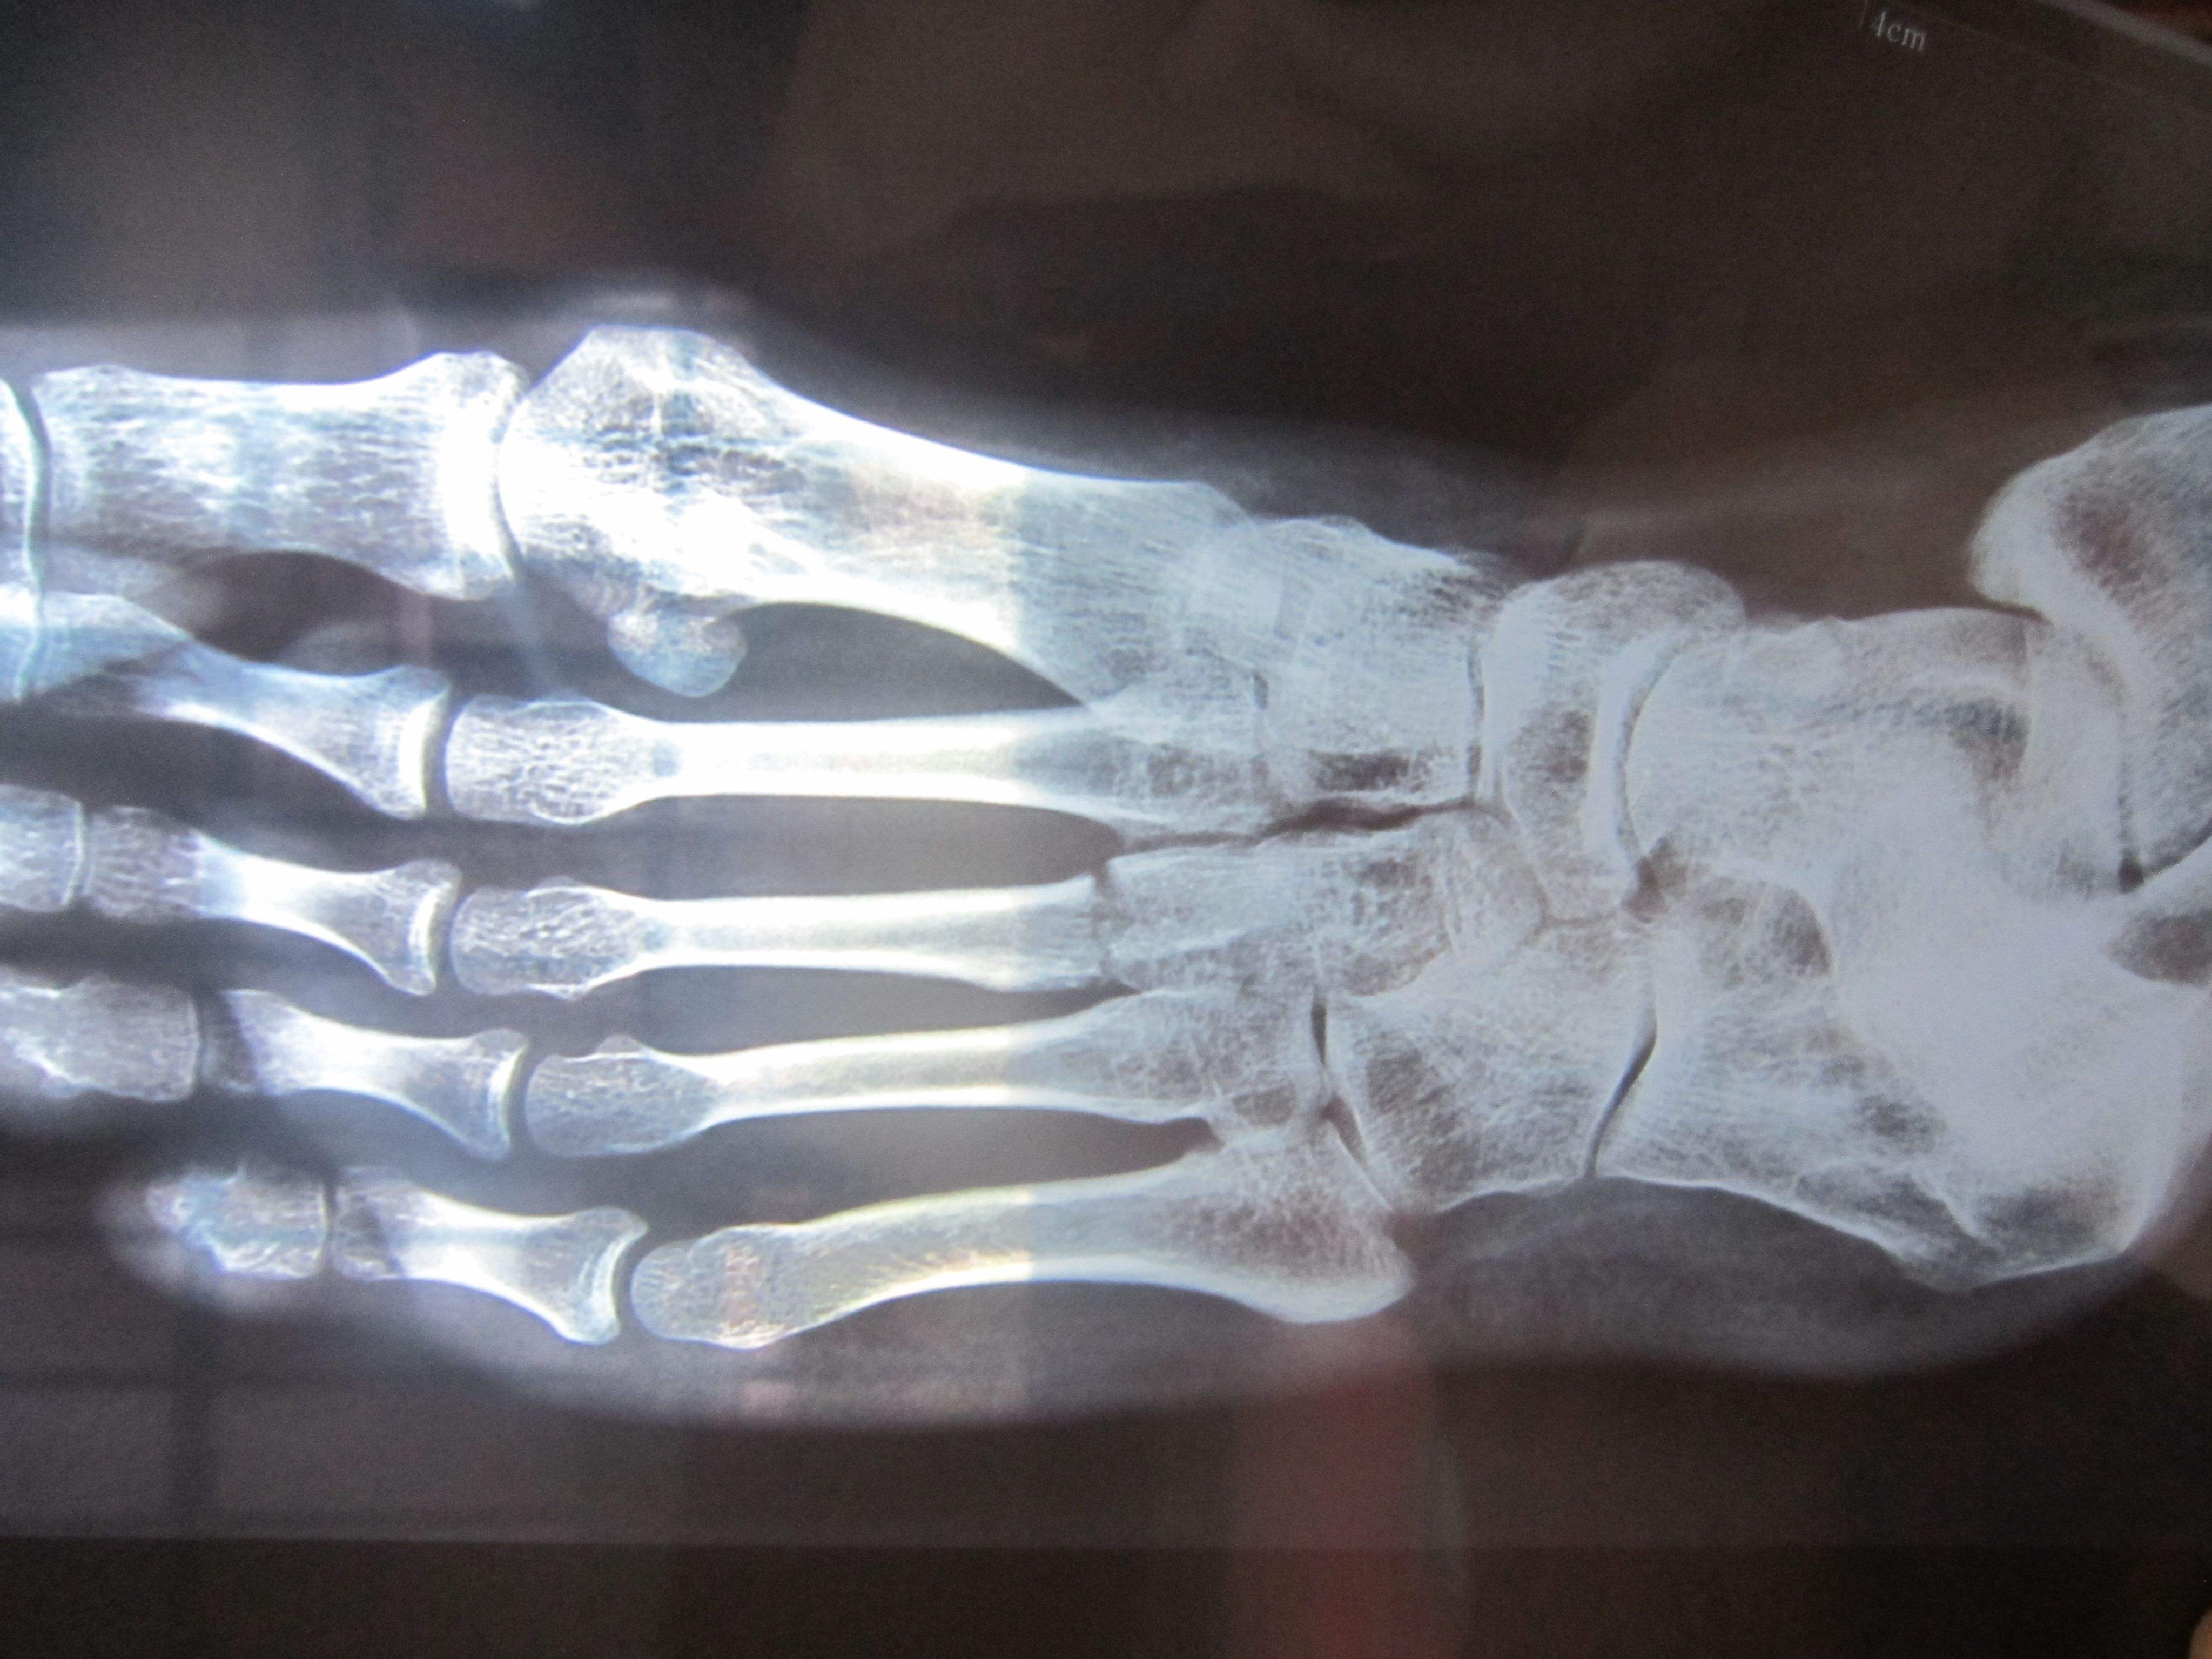

跖骨骨折多因重物打擊足背、輾壓及足內翻扭傷引起。跖骨干骨折因相鄰跖骨的支持,一般移位不大。第2、3跖骨頸部易發(fā)生應力骨折(疲勞骨折)。第5跖骨基部骨折是由于足突然內翻,腓骨短肌猛烈收縮撕脫造成,很少移位,需與該部未閉合的骨骺相鑒別。